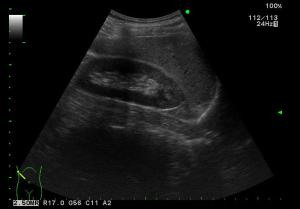

腹部超音波検査(腹部エコー検査)

超音波を腹部にあてて、返ってくる超音波を記録することにより、腹部の臓器の状態などを、観察する検査です。

痛みもなく、繰り返し検査をしても身体に影響はありません。

検査時間は約30分です。

肝臓 |

腎臓 |